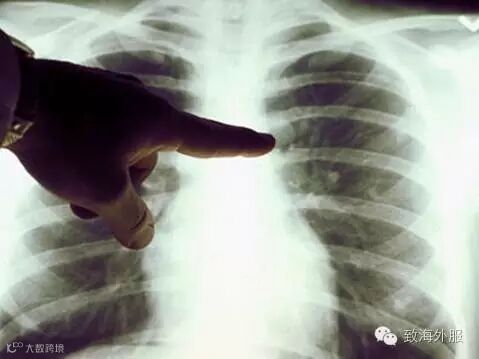

世界卫生组织(WHO)最新发布研究报告,警告未来将出现癌症病例大爆发的情况。报告说,中国的癌症目前的发病个案几乎占了全球一半,高居第一位,报告预测,到2025年,全球每年新增患癌病例将增至1900万,到2030年将增至2200万,到2035年将增至2400万,20年时间将增加近五成。全球最多人罹患的3大癌症为肺癌(180万)、乳癌(170万)、大肠癌(140万),致死率前3名的癌症则是肺癌、肝癌、胃癌。

报告认为,全球癌症发病率与死亡率呈持续上升趋势,发展中国家首当其冲,占全球新增病例的6成,年度死亡病例的7成。其中,约一半的新增肝癌病例在中国出现,尤其是由丙肝引起的肝癌。世界卫生组织呼吁,癌症没有特效药,治疗癌症的关键在于“早发现、早治疗“这六个字,从健康宣教的角度来说已经老生常谈,但能真正从思想上和行动上都做到重视癌症的预防和早发现的却是少之又少。